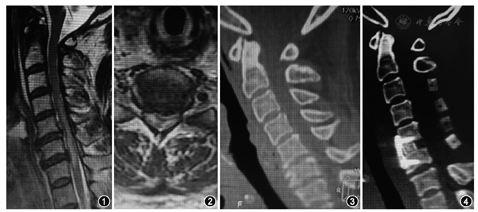

患者女性,52岁,因"甲状腺术后双手伴双下肢活动障碍1 d"于2017年5月21日急诊入院。1个月前患者颈部发现一活动结节,就诊于当地医院,行相关检查后(未行颈椎相关检查)不排除甲状腺癌。入当地医院后询问病史无颈部不适及四肢麻木无力、踩棉感等症状,颈椎及神经系统体检示:颈椎曲度变直、序列及活动度正常,颈部无压痛、叩击痛,未查及感觉异常平面,四肢感觉及运动未见明显异常,四肢腱反射正常,无病理反射。完善术前准备后行甲状腺次全切除术。患者取仰卧位,静脉麻醉状态下使用喉镜辅助顺利完成气管插管,麻醉完成后取颈椎背伸体位,充分暴露术野。手术时间约80 min。术后麻醉师唤醒患者,患者自诉双下肢伴双手活动障碍,双上肢感觉针刺、麻木感,初考虑患者意识尚未清醒,30 min后患者意识清晰,查双下肢和双手无明显活动,症状无明显改善,于当地医院急行颈椎X线检查及颈椎CT后未见明显异常,后转入普通病房详观,2 d后患者症状无明显改善,急诊转入我院行进一步治疗。入院体检:颈椎生理曲度略直,序列如常,颈部前方横切口,敷料包扎,负压引流,颈部无明显压痛、叩击痛,感觉平面在胸骨角水平,双前臂及手部感觉针刺、麻木感,四肢肌肉张力不高,双侧三角肌、肱二头肌肌力4级,双侧肱三头肌肌力3+级,双手握力0级,双下肢各肌肌力0级,双侧肱二头肌反射正常引出,双侧肱三头肌反射未引出,双侧膝腱反射、跟腱反射未引出,双侧霍夫曼征阴性,双侧巴宾斯基征阳性,余体检未见明显异常。日本骨科协会评分3分(17分法)。颈椎MRI示C4~7椎间盘向后突出,以C5~6椎间盘水平为著,黄韧带无肥厚,C4~7椎体后方水平颈髓内可见条片状T1WI低信号T2WI高信号脊髓水肿影(图1)。C5~6椎间盘水平椎管狭窄,黄韧带肥厚(图2)。颈椎CT示颈椎曲度变直,局部反张,诸椎体边缘可见骨质增生,以C6椎体为主;C4~7椎间盘突出伴相应椎管狭窄,以C5~7为著(图3)。结合相关检查及体检,诊断为颈部脊髓损伤、四肢不全瘫、颈椎管狭窄症、甲状腺术后,收入我院拟行急诊手术治疗。

完善术前准备后,入院当天在全身麻醉下(气管插管时特意告知麻醉师尽量避免颈椎背伸并使用可视喉镜辅助插管)行颈椎后路双开门椎管减压术和颈椎前路间盘切除椎管减压植骨融合内固定术。手术完成患者清醒后自述双手麻木、疼痛及下肢活动症状较术前明显改善,体检:双手握力2+级,双下肢各肌肉肌力2+级。下肢膝腱反射、跟腱反射引出,且活跃;术后第1天患者自诉双上肢及双手麻木、针刺感较术前明显缓解,双手握力3级,双下肢各肌肉肌力3级;术后1周双手握力3+级,双下肢各肌肉肌力3+级,双下肢感觉、运动恢复良好;术后2周佩戴颈托支具下地行走正常,行走平稳,四肢感觉、运动良好,四肢肌力4级,日本骨科协会评分12分。术后前3个月复查颈椎CT示颈椎内固定物位置良好(图4),无松动,椎间cage位置佳,融合确切,四肢肌力、感觉恢复如常。